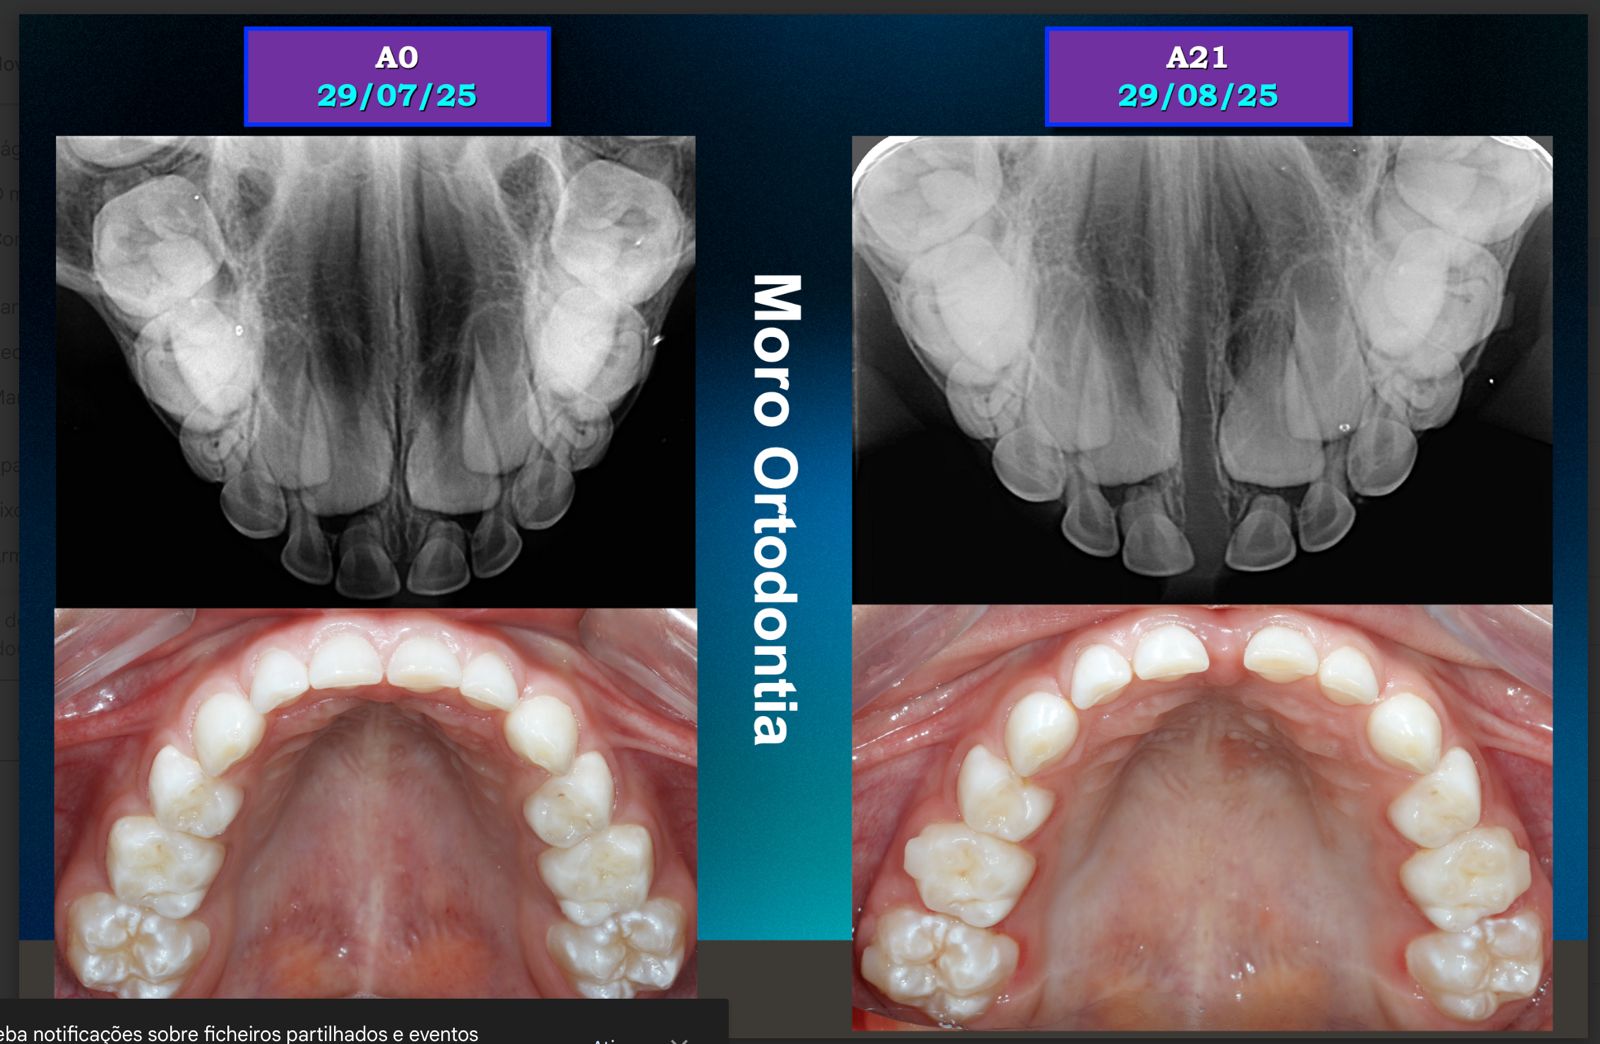

O Invisalign First é o sistema de alinhadores transparentes desenvolvido especialmente para crianças em fase de crescimento. Ele corrige problemas de mordida e alinhamento de forma confortável, removível e praticamente invisível, tornando o tratamento muito mais fácil para os pequenos e para os pais.

Sim. Os alinhadores do Invisalign First são capazes de realizar movimentos de expansão, criando espaço para os dentes permanentes nascerem de forma adequada, quando indicado pelo ortodontista.

O Novo Palatal Expander é uma evolução dos aparelhos expansores tradicionais. Integrado à tecnologia Invisalign e ao escaneamento digital iTero, ele permite ampliar o arco dentário de forma precisa, controlada e mais confortável para a criança.